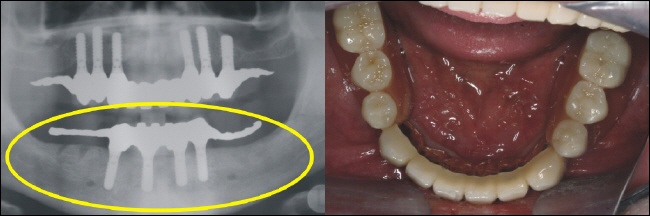

Sechs strategisch günstig positionierte Implantate wurden im Oberkiefer eingebracht, um nach der Einheilung optimalen Halt für die Prothese zu gewährleisten (gelber Kreis im Röntgenbild). |

Im Unterkiefer können die vier Implantate (Standardversorgung) im vorderen Kieferbereich eingebracht werden (gelber Kreis im Röntgenbild). |